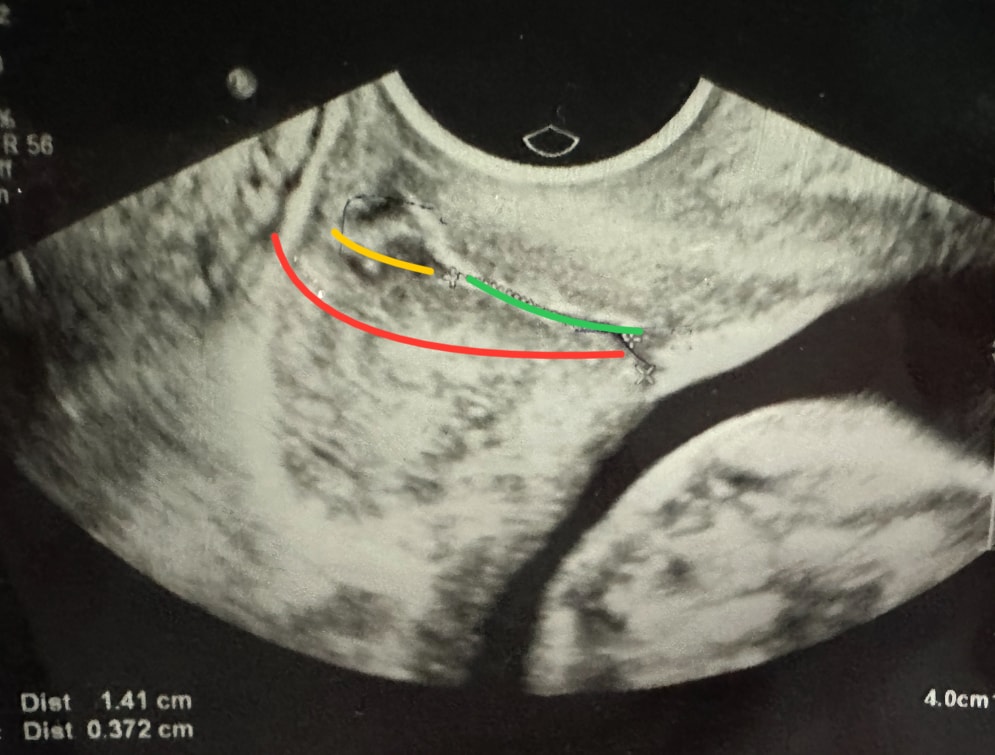

Вопрос следующий: при измерении шейки матки вам замеряли часть с полипом? У меня полип 5.4 мм и после него еще часть сомкнутой шейки (наружный зев). Врач замеряла только ту часть, где шейка сомкнута до полипа. Получается полип и дальше не замеряла. Правильно ли это?

Красным: вся шейка

Зеленым: сомкнутая часть до полипа

Желтым: полип (и после него еще кусочек сомкнутой части)